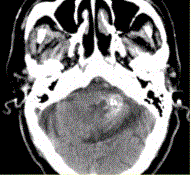

问题 男性,80岁,左耳听力下降伴头晕半年。头CT显示如下图。 可能的诊断为

选项 A.钙化灶 B.急性出血 C.动静脉畸形 D.海绵状血管瘤 E.胶质瘤 F.发育性静脉畸形 G.脑囊虫

答案 ABCDFG